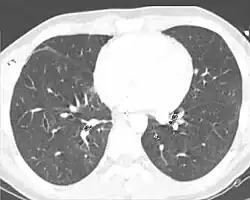

| A CT scan showing a pulmonary contusion (red arrow) accompanied by a rib fracture (purple arrow) | |

Computed tomography (CT scanning) is a more sensitive test for pulmonary contusion,[8][38] and it can identify abdominal, chest, or other injuries that accompany the contusion.[43] In one study, chest X-ray detected pulmonary contusions in 16.3% of people with serious blunt trauma, while CT detected them in 31.2% of the same people.[50] Unlike X-ray, CT scanning can detect the contusion almost immediately after the injury.[48] However, in both X-ray and CT a contusion may become more visible over the first 24–48 hours after trauma as bleeding and edema into lung tissues progress.[51] CT scanning also helps determine the size of a contusion, which is useful in determining whether a patient needs mechanical ventilation; a larger volume of contused lung on CT scan is associated with an increased likelihood that ventilation will be needed.[48] CT scans also help differentiate between contusion and pulmonary hematoma, which may be difficult to tell apart otherwise.[52] However, pulmonary contusions that are visible on CT but not chest X-ray are usually not severe enough to affect outcome or treatment.[42]